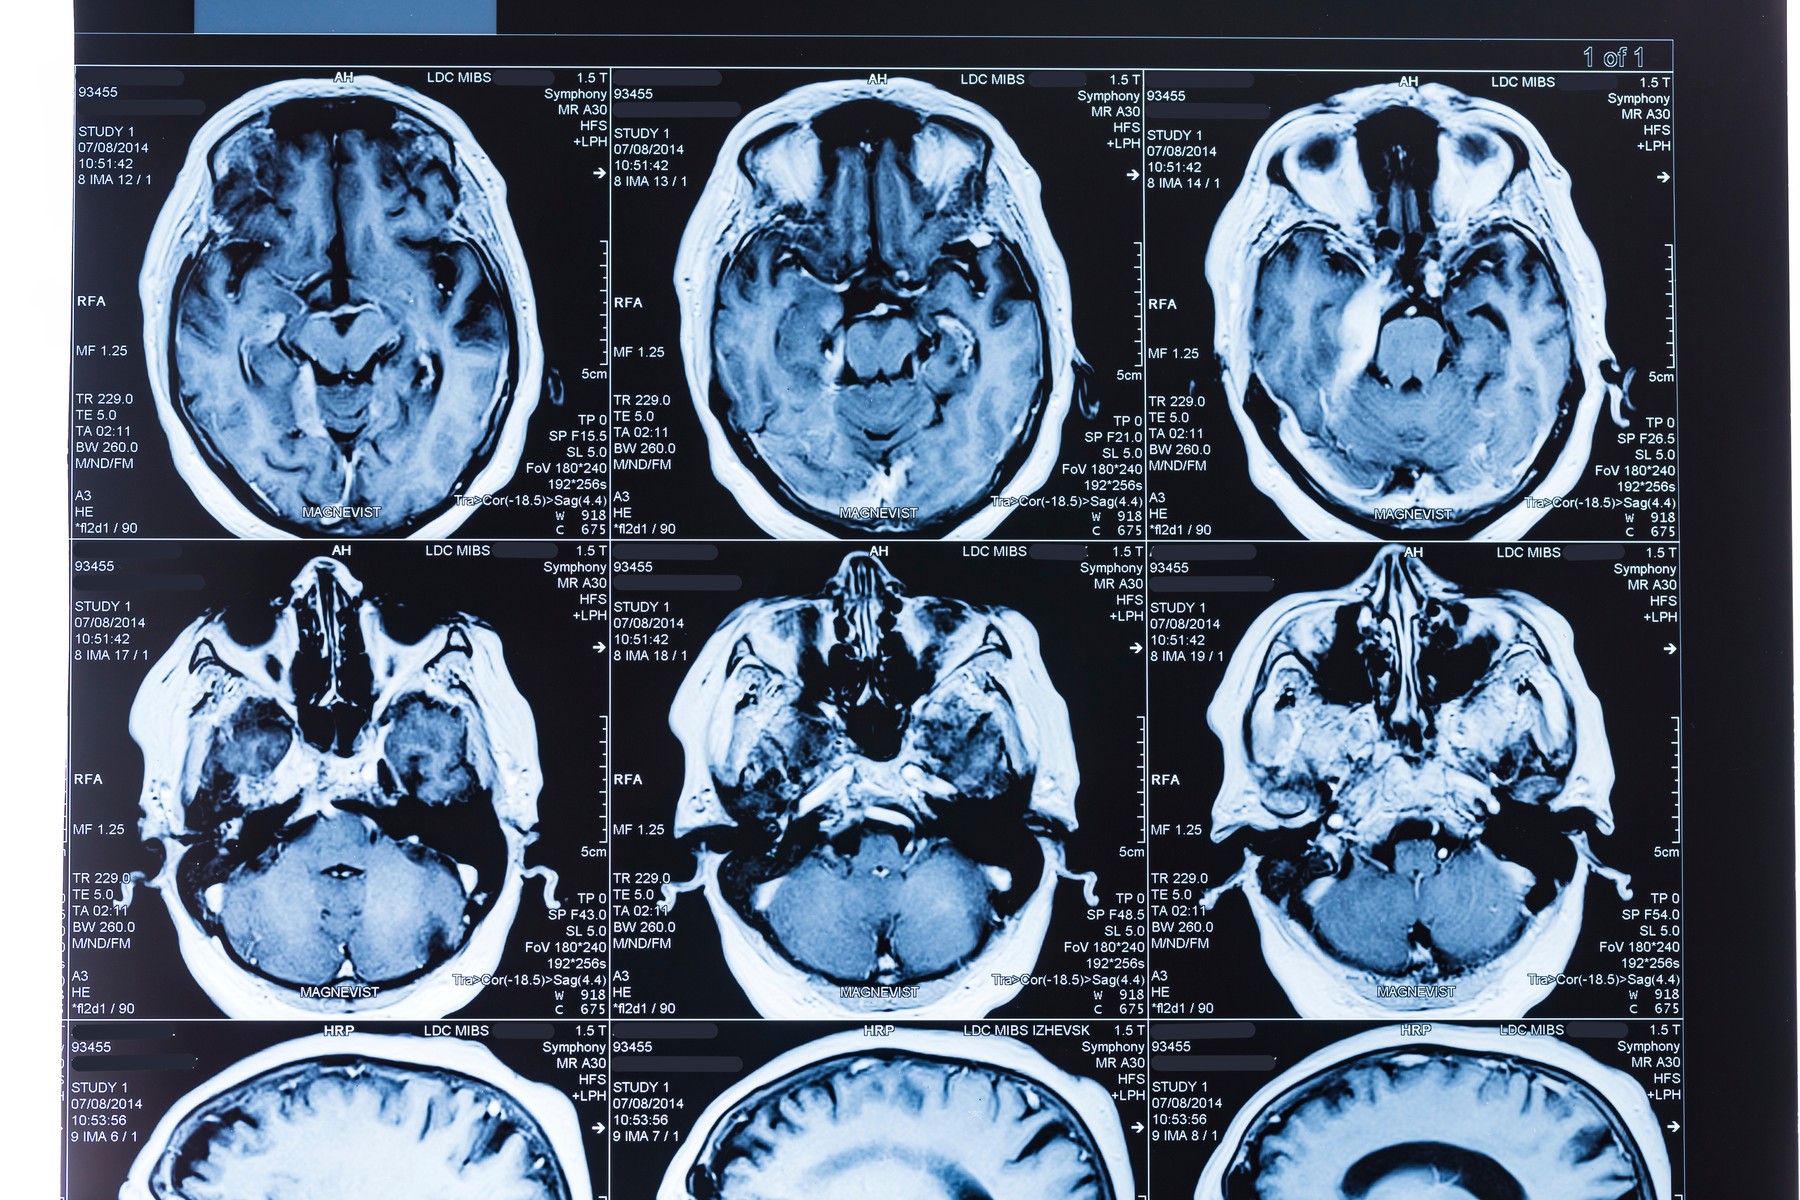

Ilustracija; Foto: WLADIMIR BULGAR / Sciencephoto / Profimedia Ilustracija; Foto: WLADIMIR BULGAR / Sciencephoto / Profimedia Ilustracija; Foto: WLADIMIR BULGAR / Sciencephoto / Profimedia Nisu dobre vesti: Šta se dešava u mozgu kad zakačiš kovid više puta autor: Nevena Dimitrijević Zdravlje 25. okt. 2022. 09:35 0 Podeli vest: Koliko infekcija oštećuje mozak Podeli vest: Oglas Poznato je da kovid 19 može da izazove kognitivne simptome kod nekih pacijenata, kao što su kratkotrajni gubitak pamćenja, poteškoće sa koncentracijom, problemi pri pamćenju reči i takozvana moždana magla koja se povezuje sa dugim kovidom. Međutim, dok su se mnoge studije u prethodno vreme fokusirale na pacijente hospitalizovane zbog teških simptoma bolesti, sada je postalo očigledno da su mnogi pacijenti sa kovidom imali simptome i nakon blagog oblika bolesti.Nova studija nedavno objavljena u naučnom časopisu Nature sugeriše da čak i blagi slučajevi kovida mogu uticati na mozak. Koristeći magnetnu rezonancu, istraživači su uporedili mozak istih pacijenata pre i nakon što su se zarazili kovidom. Otkrili su promene u oblastima mozga koje bi mogle da se povežu sa uobičajenim simptomima, uključujući gubitak mirisa i ukusa, glavobolje i probleme sa pamćenjem, piše congnitivefxusa. Čak i blagi slučajevi utiču na mozak Ova studija je jedna od prvih koja se fokusira na pacijente sa blagim oblikom bolesti. Sa skoro 800 volontera to je ujedno i najopsežnija studija o kovidu koja uključuje skeniranje mozga. Istraživači sa Univerziteta u Oksfordu primenili su kognitivne testove i skenirali mozak 785 pacijenata starosti od 51 do 81 godine. Većina njih je imala lakši oblik bolesti, ali je 15 osoba hospitalizovano zbog kovida, a dvema je bila potrebna potrebna intenzivna nega. Budući da je studija skeniranja mozga inače počela pre pandemije, ovi pacijenti su prvobitno skenirani između 2014. i 2019, a zatim ponovo četiri do pet meseci nakon dijagnoze kovida. Oglas Šta je studija pokazala Rezultati jasno pokazuju da čak i blagi slučajevi kovida mogu imati uticaj na mozak. Manje od šest meseci nakon infekcije neki pacijenti su izgubili do dva odsto zapremine mozga i debljine sive mase u određenim delovima mozga. Ovi gubici mogu objasniti neke simptome koje imaju pacijenti sa kovidom. Na primer, orbitofrontalni korteks - koji se nalazi na prednjem delu mozga, odmah iznad očnih duplji – povezan je sa senzornim oblastima, što može objasniti gubitak mirisa i ukusa. Pored toga, parahipokampalni girus, koji se nalazi neposredno iznad hipokampusa na dnu vrata, igra vitalnu ulogu u pamćenju, donošenju odluka i to objašnjava simptome kao što su moždana magla, gubitak pamćenja i anksioznost.Pritom, svi gubimo volumen mozga kako starimo, ali dva odsto gubitka je skoro 10 puta veći gubitak od onog koji svake godine pretrpe starije odrasle osobe usled normalnog starenja. Pored toga, pacijenti su se više mučili na kognitivnim testovima nakon kovida, verovatno uzrokovanih atrofijom malog mozga. Pacijentima je trebalo više vremena da odgovore na pitanja koja su merila pažnju, sposobnost vizuelnog opažanja i brzinu obrade. Nije bilo razlika u vezi sa pamćenjem, vremenom reakcije ili testovima rasuđivanja.Za sada se još uvek ne zna da li je šteta na mozgu posle blagog kovida privremena ili trajna.BONUS VIDEO: Šta je postkovid video-cdn src="https://best-vod.umn.cdn.united.cloud/stream?asset=potpunonovadijagnozatajepostkovid-novas-worldwide&stream=hp3500&t=0&player=m3u8v&sp=novas&u=novas&p=n0v43!23t001" video-id="3128049"] blagi kovid kovid mozak posledice Pratite nas na društvenim mrežama: Koje je tvoje mišljenje o ovoj temi? Učestvuj u diskusiji ili pročitaj komentare Budite prvi koji će ostaviti komentar Pošalji komentar Pročitaj komentare (0)